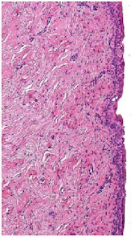

What organ is in the image provided and what phase of the estrous cycle is it in?

vagina in proestrus